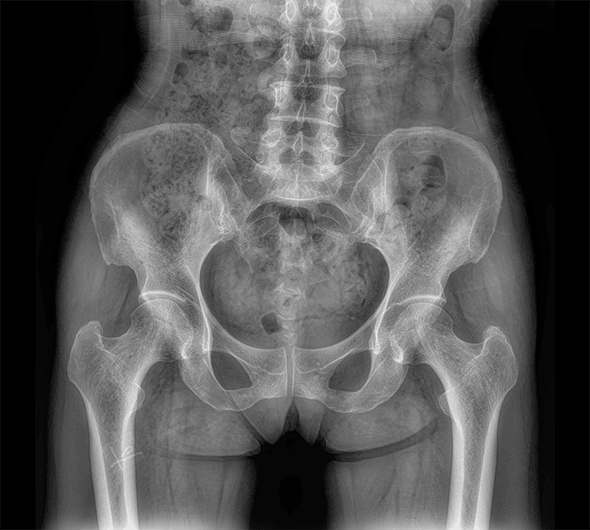

临床图像

原厂优质影像链,搭载直接生长式碘化铯非晶硅平板,带来更加清晰锐利的图像效果。